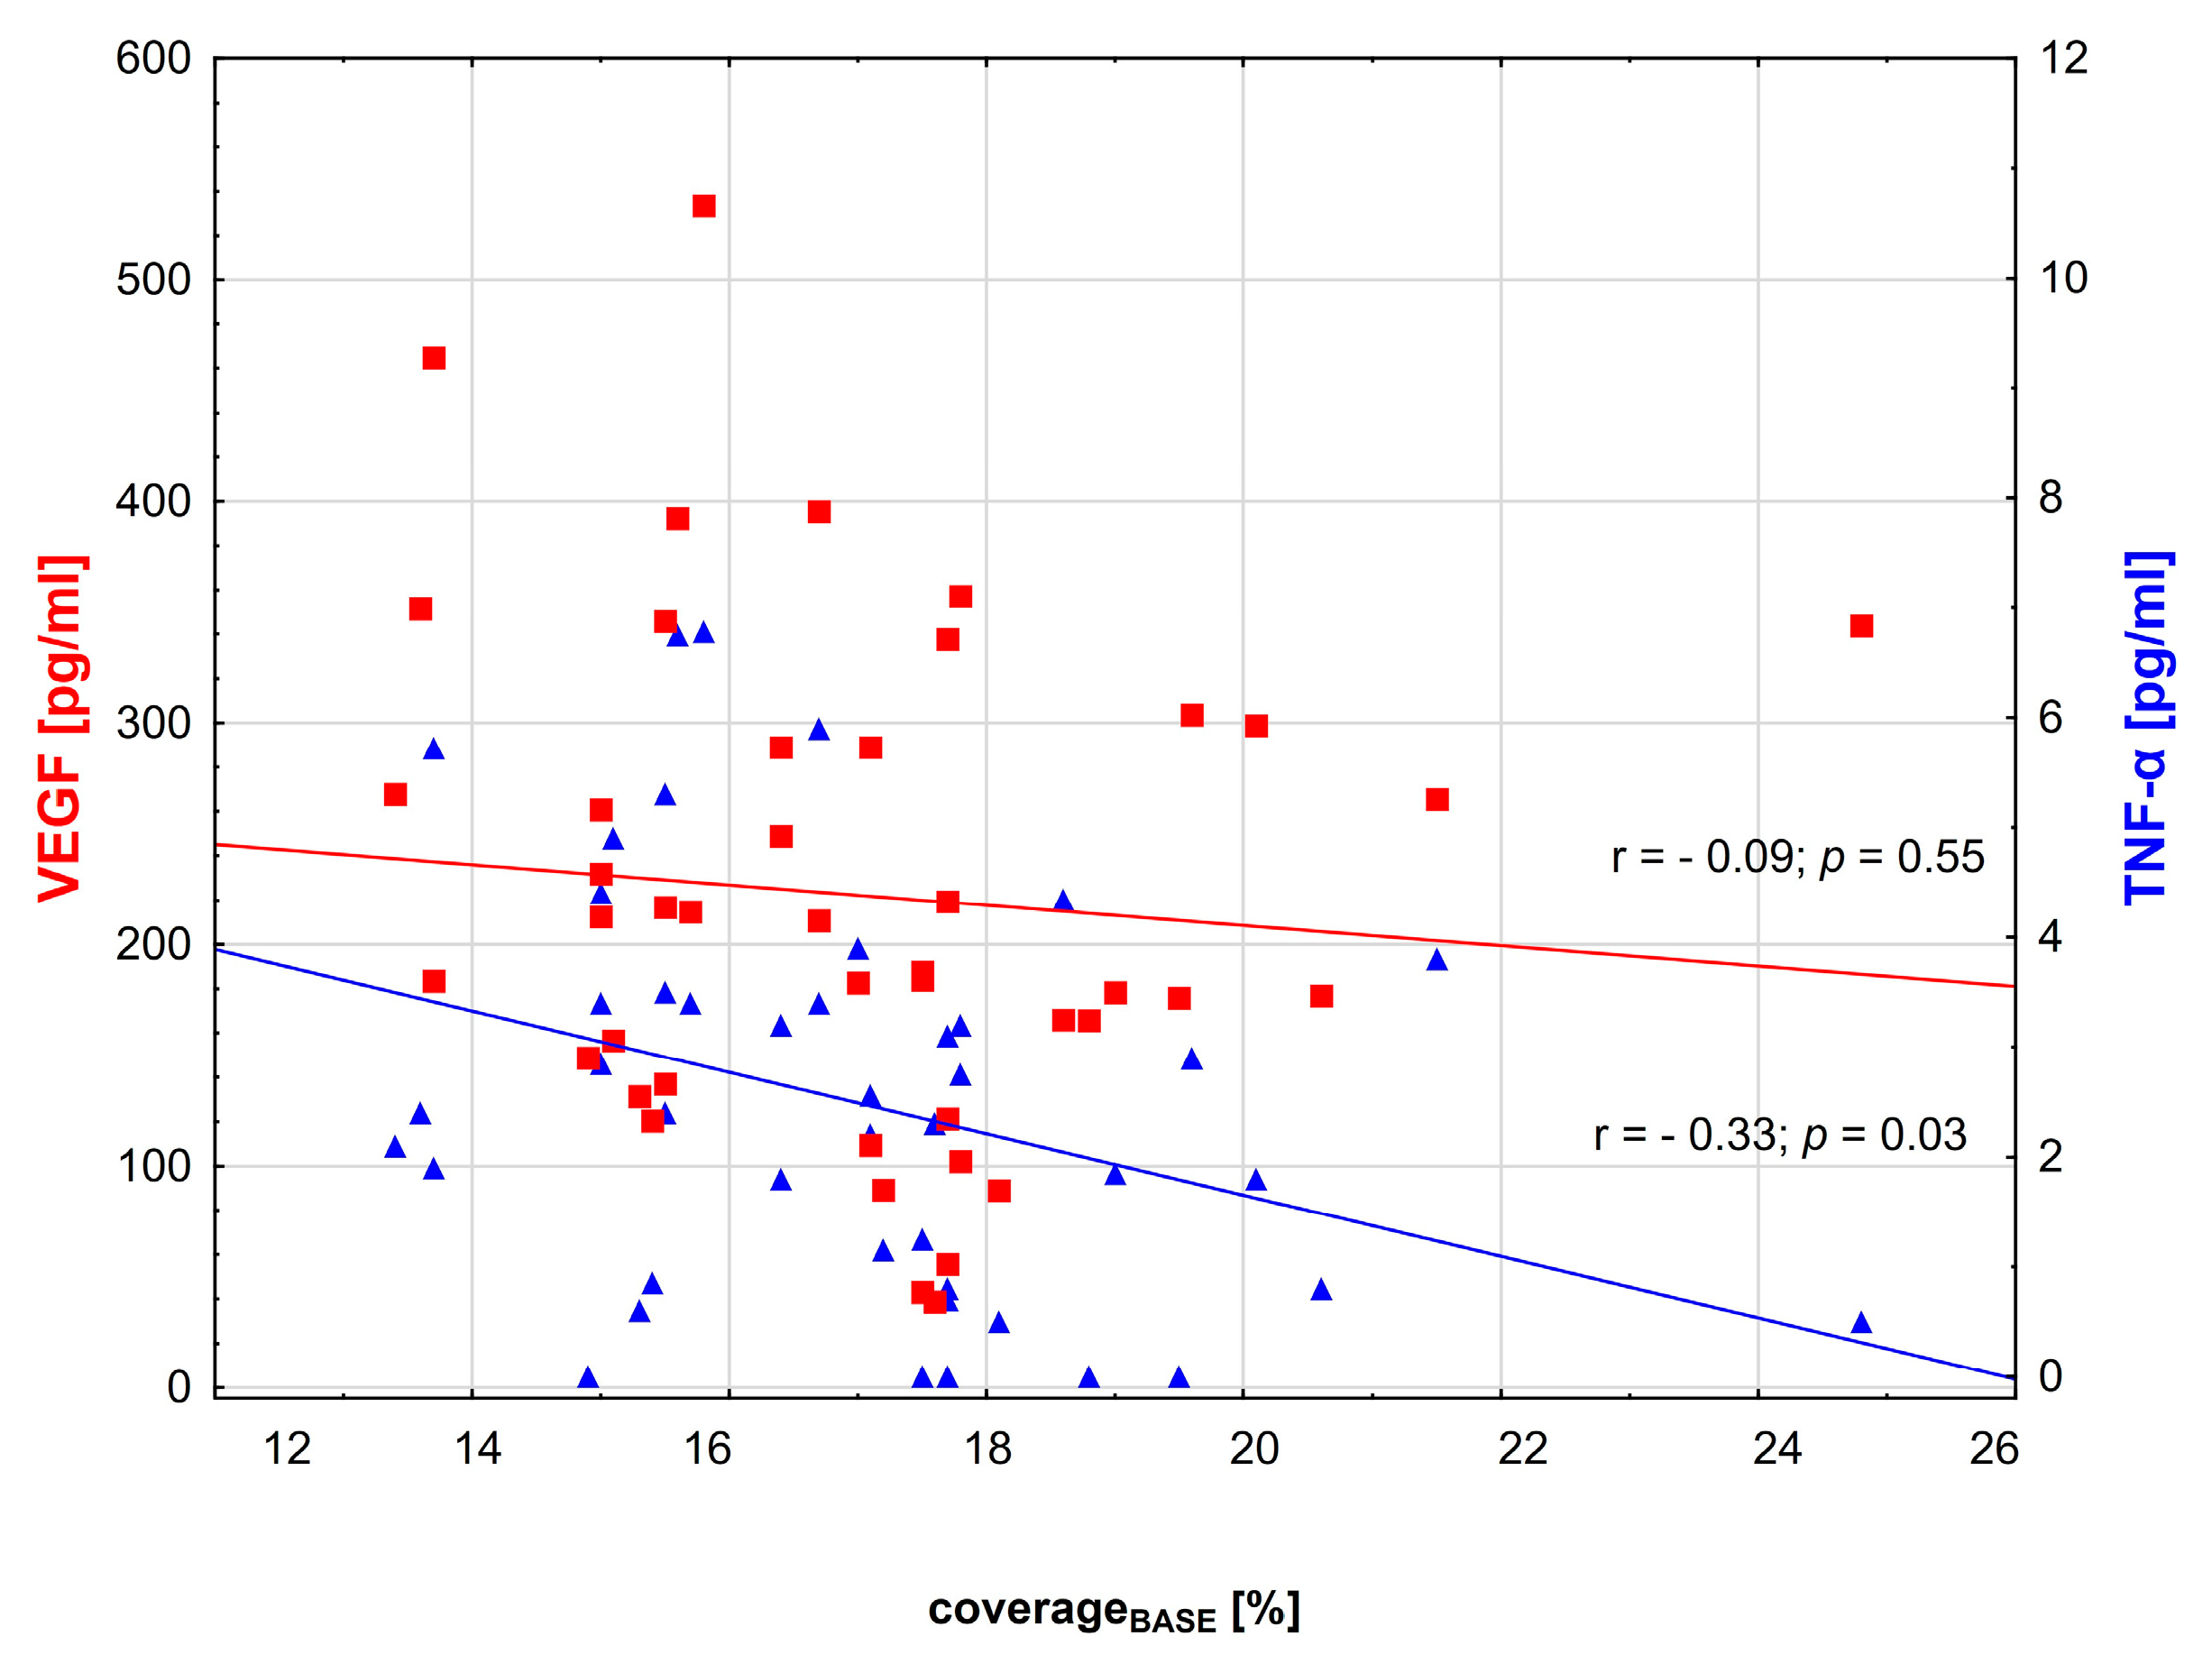

3.2. Correlations between Variables

| TNF-α [pg/mL] | 2.4 (0–6.78) | 3.4 (0–6.8) | 1.25 (0–4.3) | 0.001 |

| VEGF [pg/mL] | 211.75 (38.8–533.73) | 232.2 (120.4–533.7) | 176.8 (38.81–357.4) | 0.03 |